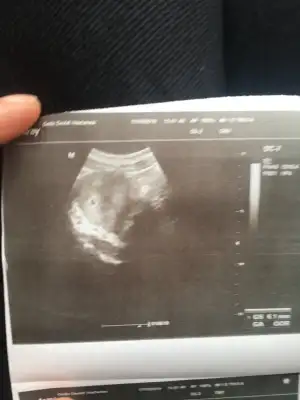

Kızlar doktora geldim bugün kan veririm diye ama kese göründü 5haftalık miniğim❤️❤️❤️

• EDC07561-CE0B-49C1-A6FE-91878C14D20B.webp

Canım valla ilk yaptığımda 42.3dü bugünde kpntrole gittim kan veririm diye düşünüyodum kese göründüğü için kan vermene gerek yok dedi doktor🤗🤗 3hafta sonra kalp atışını duyarız dedi🤲🏻🤲🏻 Bakalım şimdi iyi bi doktor araştırıyorum doğumumu falan yapıcak nasip olursa inşallah